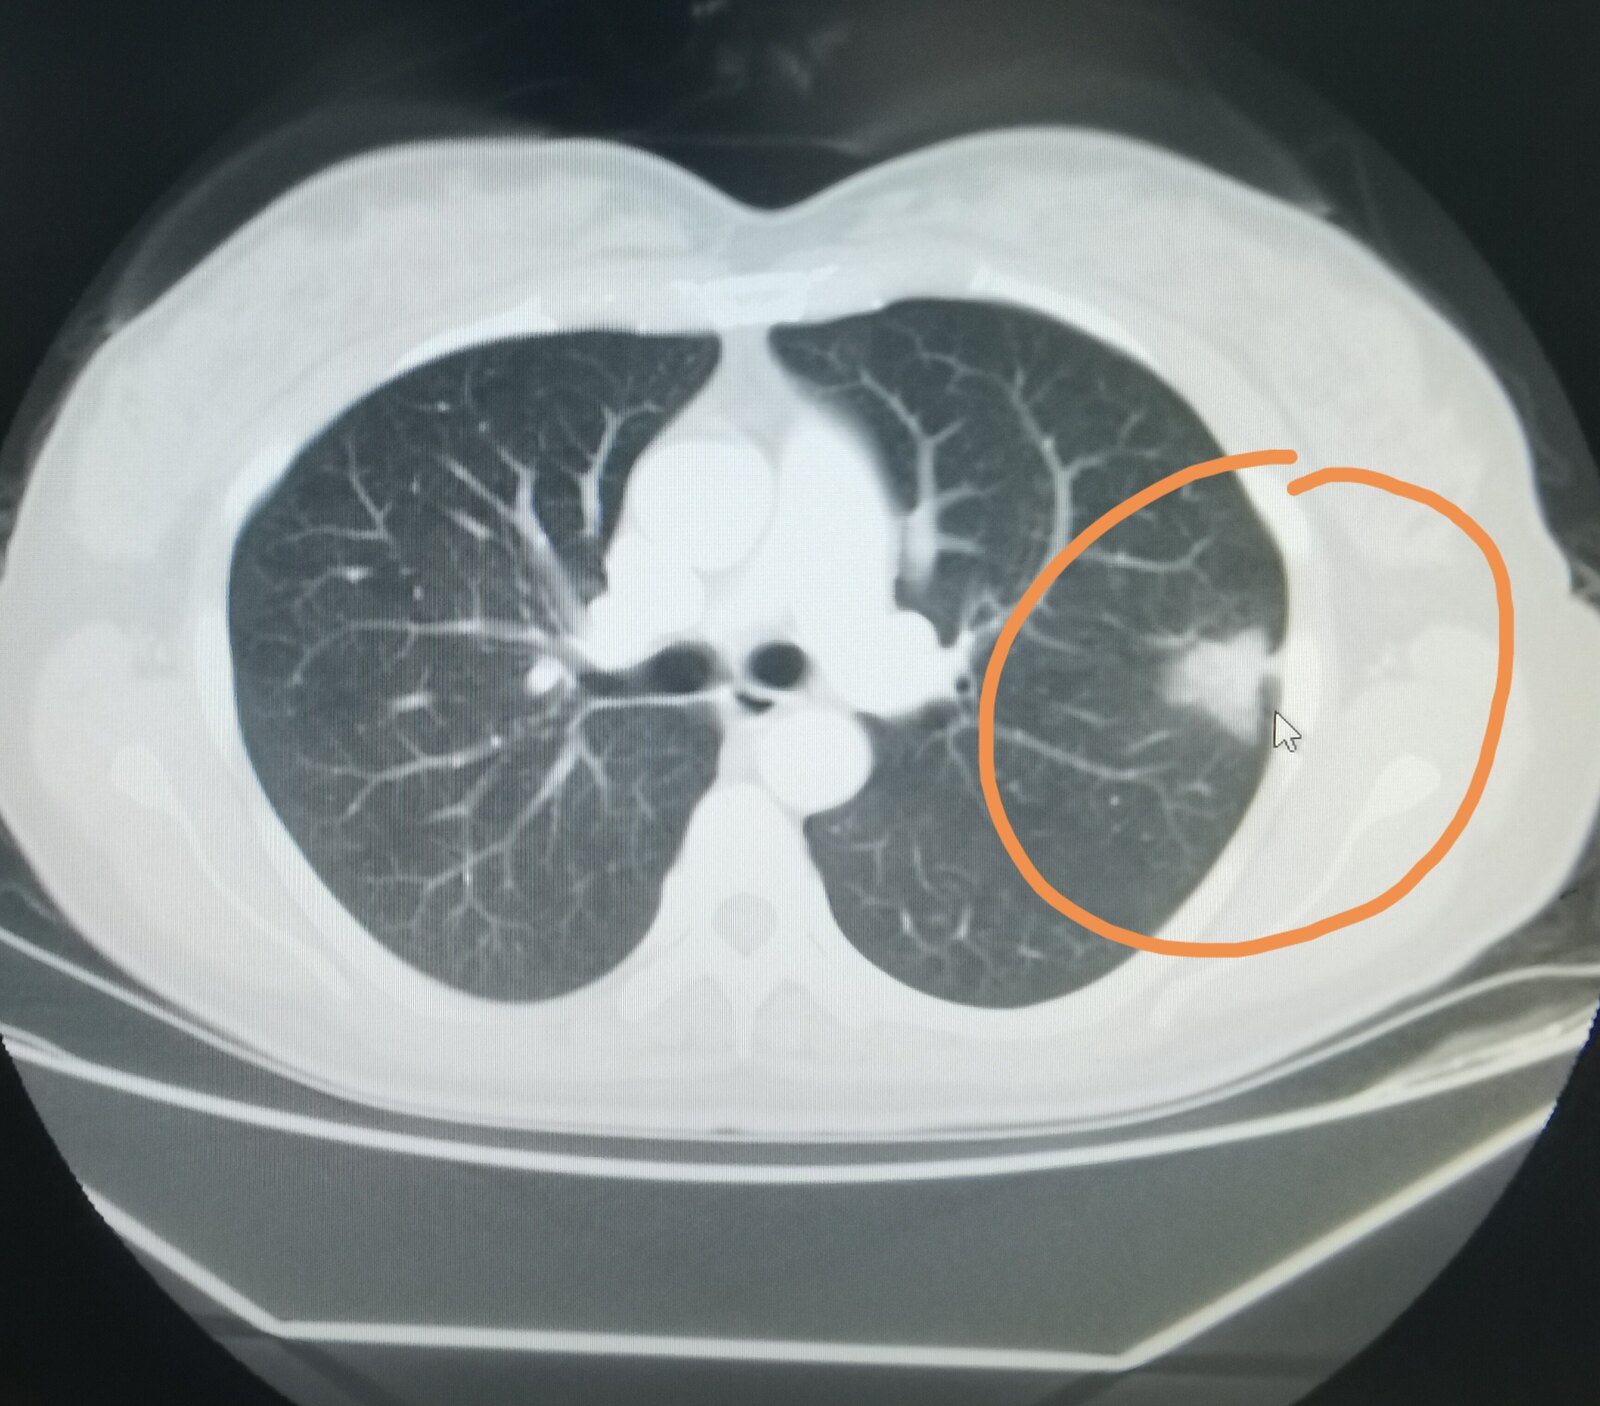

前段时间有一位45岁的女士在丈夫的陪伴下找我看病,她参加了学校组织的体检,刚开始做了一个胸片,胸片显示左肺有阴影,于是她到当地医院又拍了一个CT ,CT发现左上肺有一个结节。

我看到了她当地医院的片子,觉得这个病变首先考虑是肺癌,符合肺癌的CT影像学特征。我建议她住院,系统检查,如果没有禁忌症,这个病变应该手术切除。她回去商量好,给我留言,打算在我这里治疗。我给她安排好床位后,住了进来。经过系统检查,全身没有发现有转移,45岁身体状态肯定也是不错的,于是给她做了手术,手术病理就是显示是一个肺腺癌,其中支气管旁淋巴结有一个已经转移了。

这个女士之前也参加过单位体检,拍的都是胸片,没有发现肺部有问题,我也详细问了这位女士,她是教师,自己不抽烟也没有接触二手烟,也没有肺癌病史的亲人,这么看起来,她并不属于肺癌高危人群。 按照指南推荐,她不需要每年查胸部CT排查肺癌,但就是这样一个没有肺癌高危因素的人,恰恰得了肺癌。 她的病灶不是一两年内长起来的,我觉得要提前三、四年拍CT,就能看到当时比较小的磨玻璃结节, 只不过她之前的从来没有拍过CT而已。通过这个病例给大家一个提示,即便自己不属于肺癌高危人群,如果以前从来没有照过CT,我觉得还是拍个CT留个底儿好一点。 如果肺癌在磨玻璃阶段就把这东西切掉,那治疗效果肯定会很好,不会影响寿命。